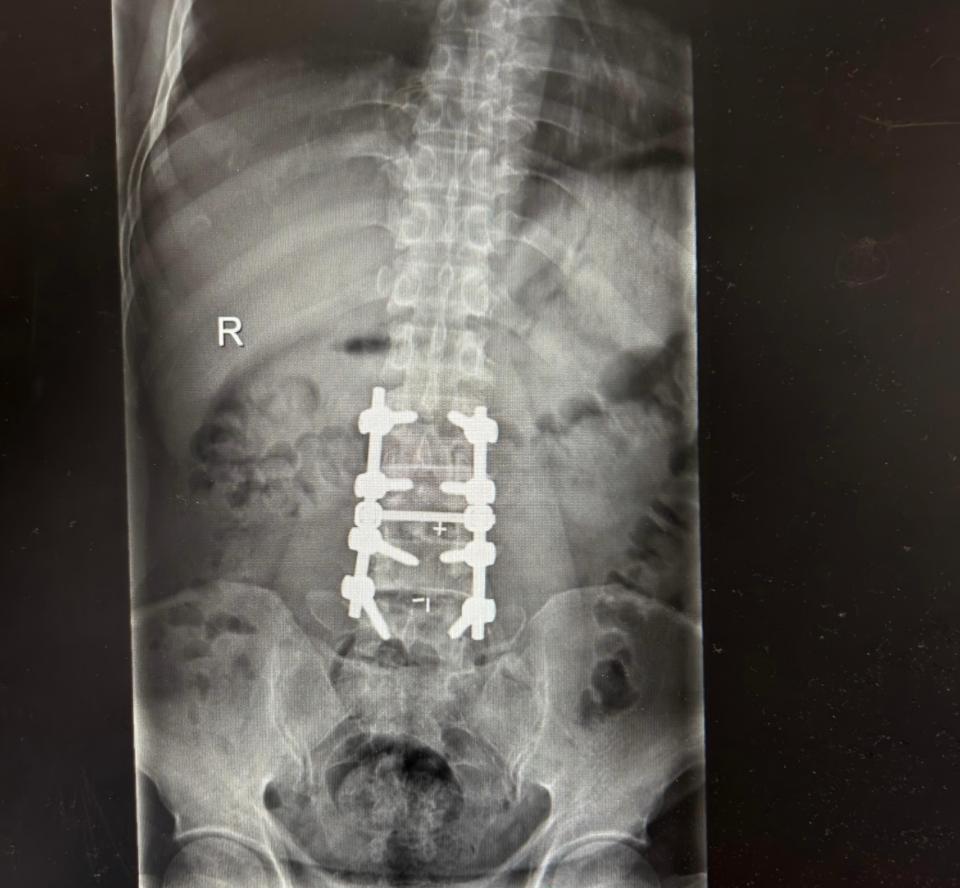

针对李师傅的病情,医生为他施行了钉棒融合内固定术。该手术可以解除神经压迫、稳定脊柱、恢复椎间高度,从根本上解决腰椎问题。术后,李师傅原有的放射性疼痛显著缓解。他在恢复中感叹:“专业的人做专业的事,感觉就是不一样。之前疼得难受,现在终于不疼了。”